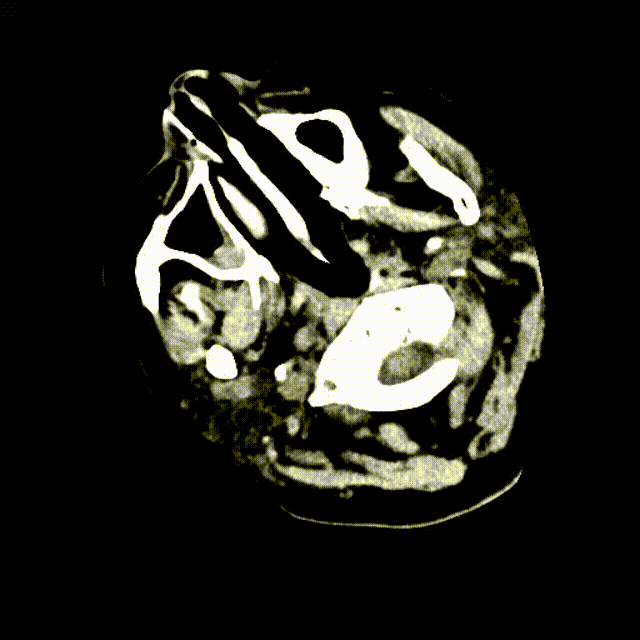

复查头颅CT提示广泛蛛网膜下腔出血,脑室扩张。基底动脉远端扩张请结合临床。急诊CTA提示:基底动脉两枚动脉瘤(图1)。